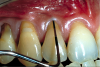

Fig 4. Patient presented with no gingiva on tooth No. 6 and 1.5 mm of gingiva on tooth No. 7 with increasing gingival recession. Probing of each tooth to 3 mm indicated a lack of attached gingiva.

Figure 4

A male patient in his 30s presented for treatment of increasing recession he had had over his lifetime. Upon examination, a complete lack of gingiva on the facial of tooth No. 6 was observed. Although he had about 1.5 mm of gingiva on the facial of tooth No. 7 (Figure 4), both teeth probed to 3 mm. This indicated an absence of attached gingiva on the facial of these teeth in addition to increasing recession.

With a low lip line, the patient was not concerned about esthetics, and he was not experiencing root sensitivity. It was determined and agreed that a FGG was the best option for him in order to increase the amount of gingiva and limit further recession.